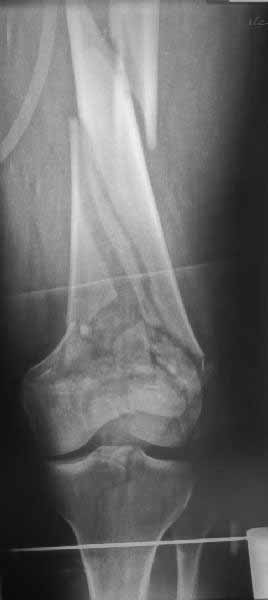

Представленный снимок не дает полную информацию. Там вроде простой перелом, но на самом деле, кроме смещенного (латерального, возможно медиального?) мыщелка на второй проекции имеется медиальный короткий дистальный фрагмент в флексии. Надо было сделать прямой снимок с захватом малоберцовой, который ориентировал бы стороны. Без КТ обычный снимок в дистракции поможет разобраться в топографии фрагментов.

Кстати, из вашего снимка, если отмечены вашим рентгенологом правильно, тогда получается снимок левого колена, и, соответственно, длинный переходящий в диафиз мыщелковый фрагмент находится медиально. Если так, тогда меняется сценарий фиксации!!!

Сразу не обратил ваше внимание именно на это, что сломаны оба мыщелка, и больший является именно медиальным мыщелком, а пластины ставятся по латеральной стороне, соответственно, в этом медиальном мыщелке от пластины останутся только концы винтов, которые не обеспечат достаточной фиксации мыщелка.

И не обратите, коллега, пока не сделаете четкие анфасные снимки (лучше с дистракцией) где будет четко визуализироваться малоберцовая кость. Думается, что и КТ здесь будет уместно, дабы не пропустить возможное флексионное повреждение (перелом Hoffa).